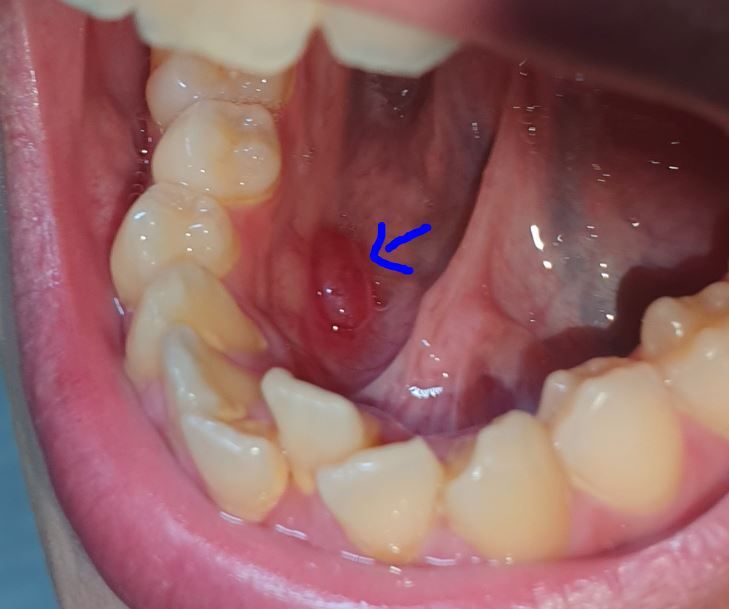

입안 바닥에 덩어리가 느껴집니다

처음 발견한지는 한 4일정도 되었고

크기는 1.5cm 만한거 같습니다

혀로 밀었을 때 말캉한 느낌이 들고 통증은 없습니다

어떨때는 빨갛게 어떨때는 하얗게 변하기도 하네요

크기도 조금씩 달라지는거 같은데 어떨 땐 작아졌다 어떨땐 커졌다 합니다

혀밑에 생긴 점액종으로 추정됩니다. 점액종은 침이 나오는 작은 구멍이 막혀 침이 고여 부풀어 오르는 것으로 생각하시면

됩니다. 저절로 터지기도 합니다. 일반 치과 보다는 구강외과 전문의가 치료하는 치과에 가는 것이 좋습니다.